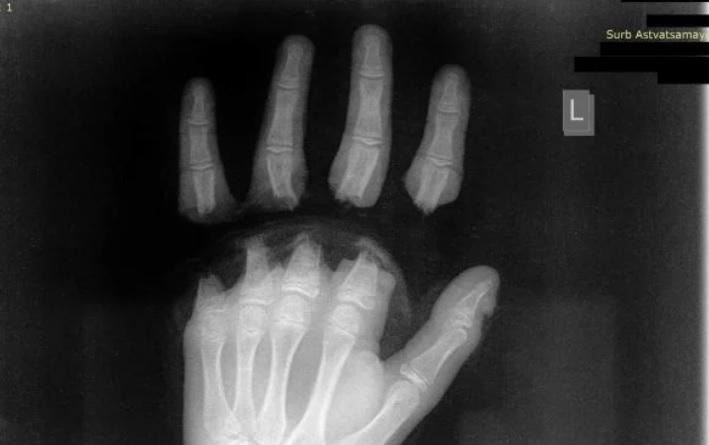

«Սուրբ Աստվածամայր» ԲԿ է ընդունվել 12 տարեկան երեխա՝ ձեռքի չորս մատների ամպուտացմամբ (անդամահատված): Այս մասին հայտնում է բկ-ի խոսնակ Գևորգ Դերձյանը:

Երեխան տասը ժամ վիրահատվել է, «Սուրբ Աստվածամայր» ԲԿ-ի պլաստիկ վիրաբույժները կատարել են ձեռքի մատների ռեպլանտացիա: